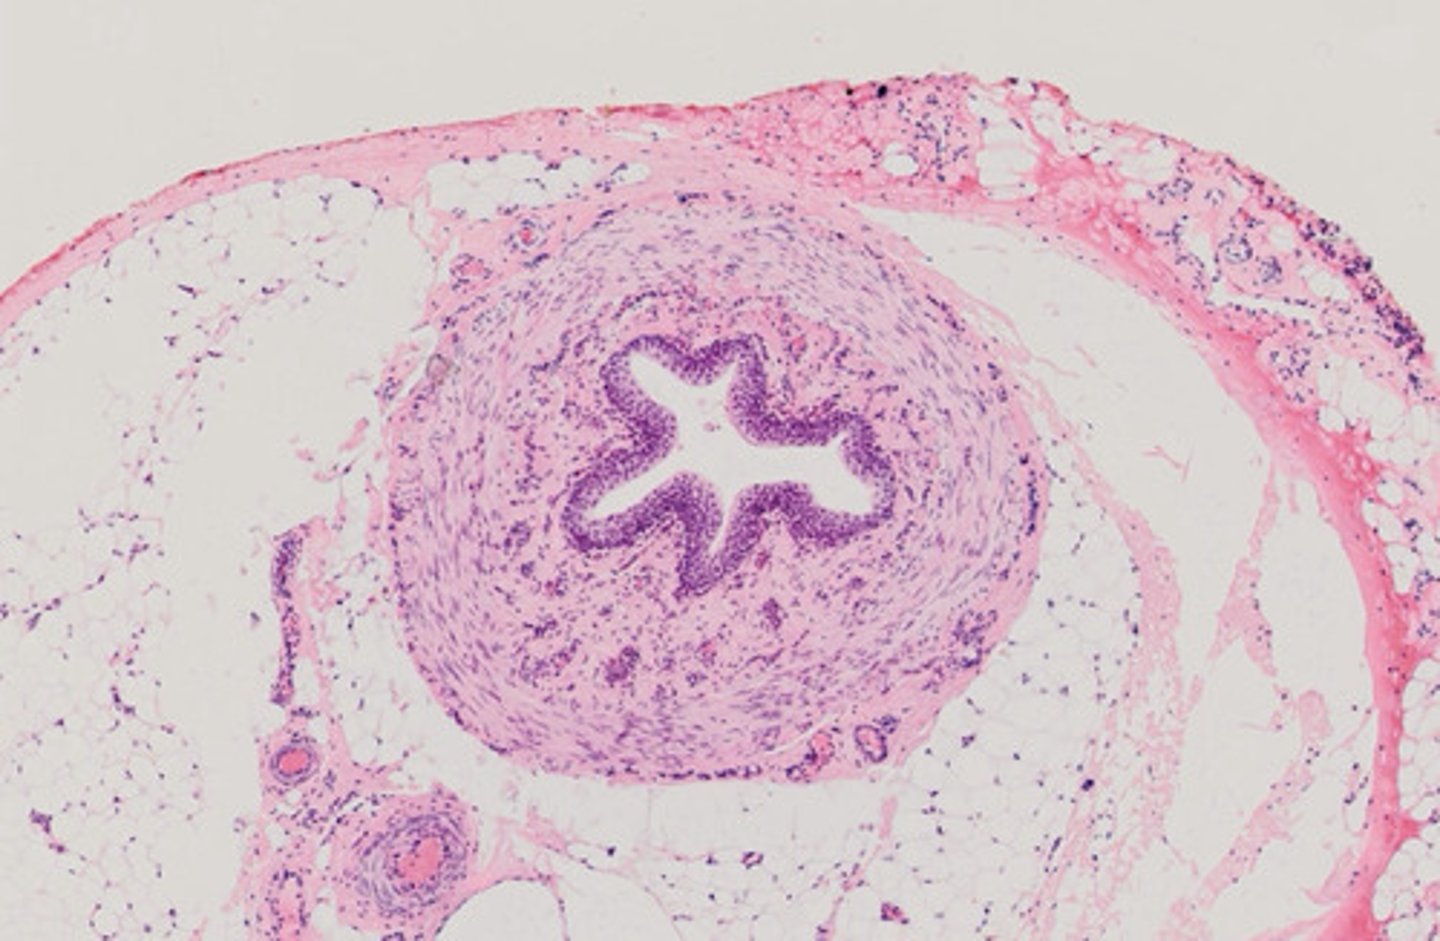

Tętnica typu mięśniowego i żyła (H+E)

Moczowód (H+E)